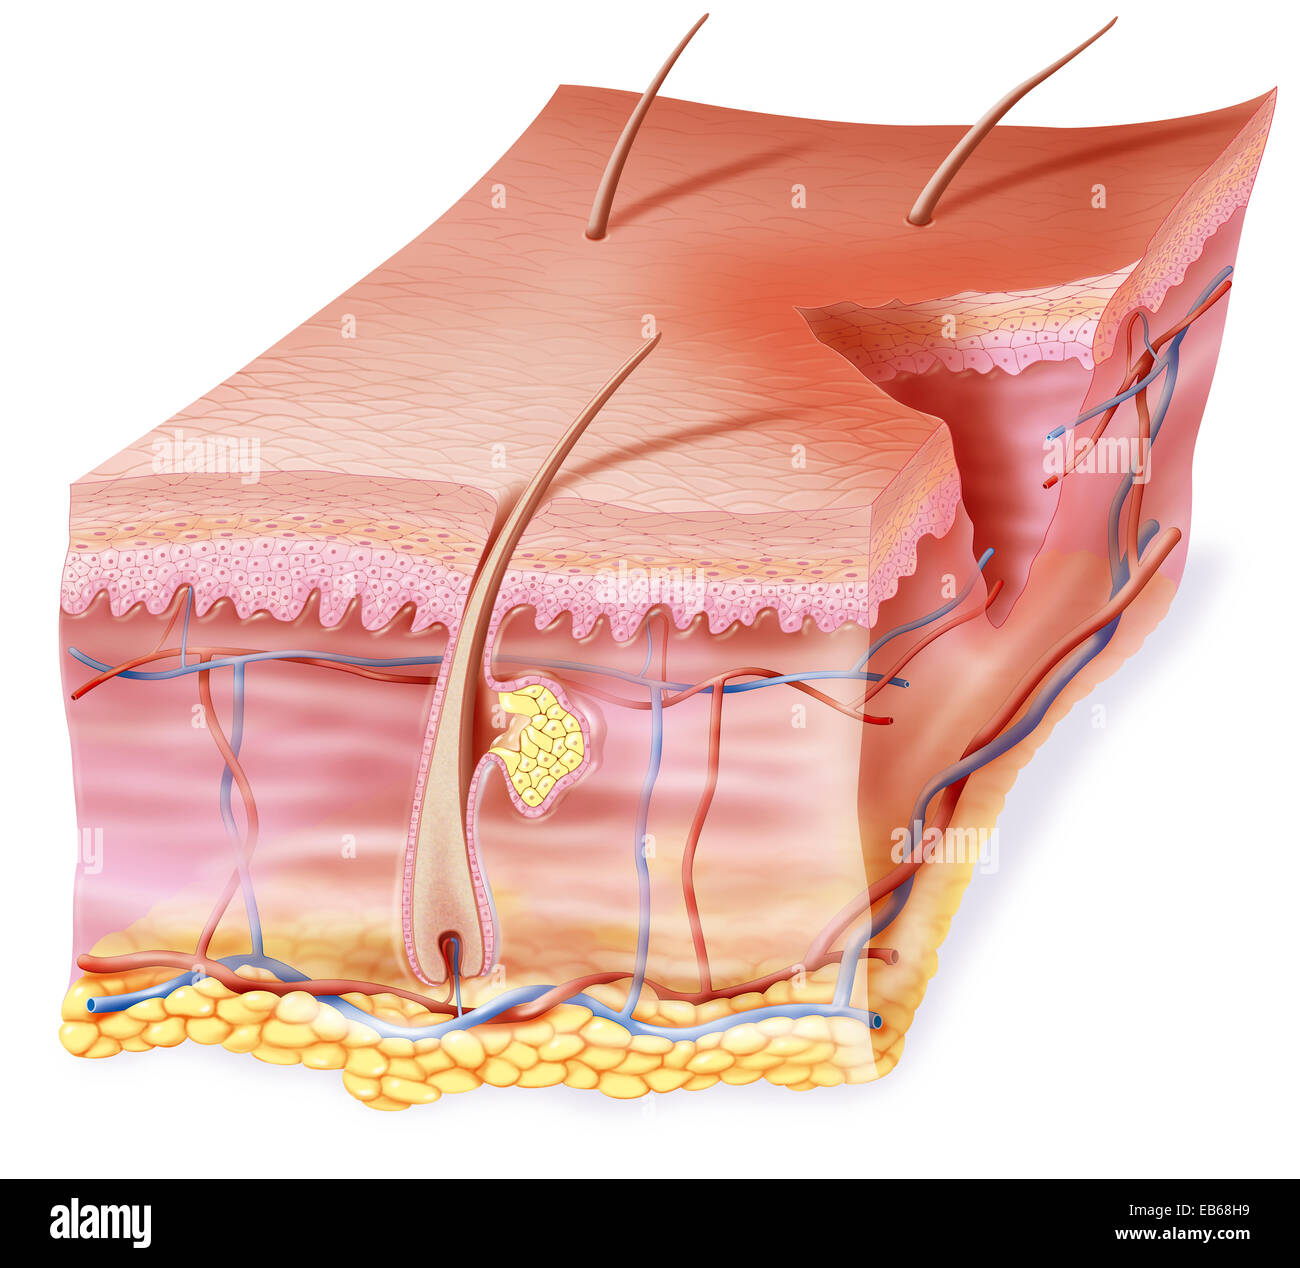

SCAR DRAWING Stock Photohttps://www.alamy.com/image-license-details/?v=1https://www.alamy.com/stock-photo-scar-drawing-75741327.html

SCAR DRAWING Stock Photohttps://www.alamy.com/image-license-details/?v=1https://www.alamy.com/stock-photo-scar-drawing-75741327.htmlRMEB68RB–SCAR DRAWING

SCAR DRAWING Stock Photohttps://www.alamy.com/image-license-details/?v=1https://www.alamy.com/stock-photo-scar-drawing-75741328.html

SCAR DRAWING Stock Photohttps://www.alamy.com/image-license-details/?v=1https://www.alamy.com/stock-photo-scar-drawing-75741328.htmlRMEB68RC–SCAR DRAWING

SCAR DRAWING Stock Photohttps://www.alamy.com/image-license-details/?v=1https://www.alamy.com/stock-photo-scar-drawing-75741331.html

SCAR DRAWING Stock Photohttps://www.alamy.com/image-license-details/?v=1https://www.alamy.com/stock-photo-scar-drawing-75741331.htmlRMEB68RF–SCAR DRAWING